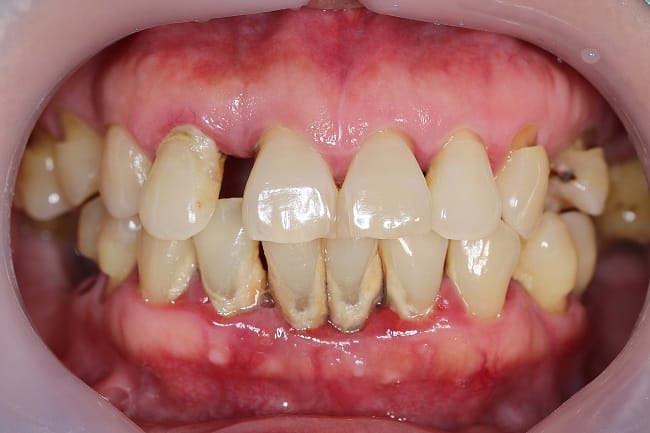

Gejala Periodontitis

Gejala periodontitis bisa beragam dan tergantung pada perkembangan peradangan yang terjadi gusi dan gigi. Namun, ada beberapa gejala atau keluhan yang umum dialami oleh penderita periodontitis, yaitu:

- Penumpukan plak dan karang pada gigi

- Gusi turun atau menyusut sehingga membuat gigi terlihat lebih panjang

- Gusi berwarna kemerahan atau keunguan

- Gusi bengkak dan mudah berdarah

- Gigi goyang atau tanggal